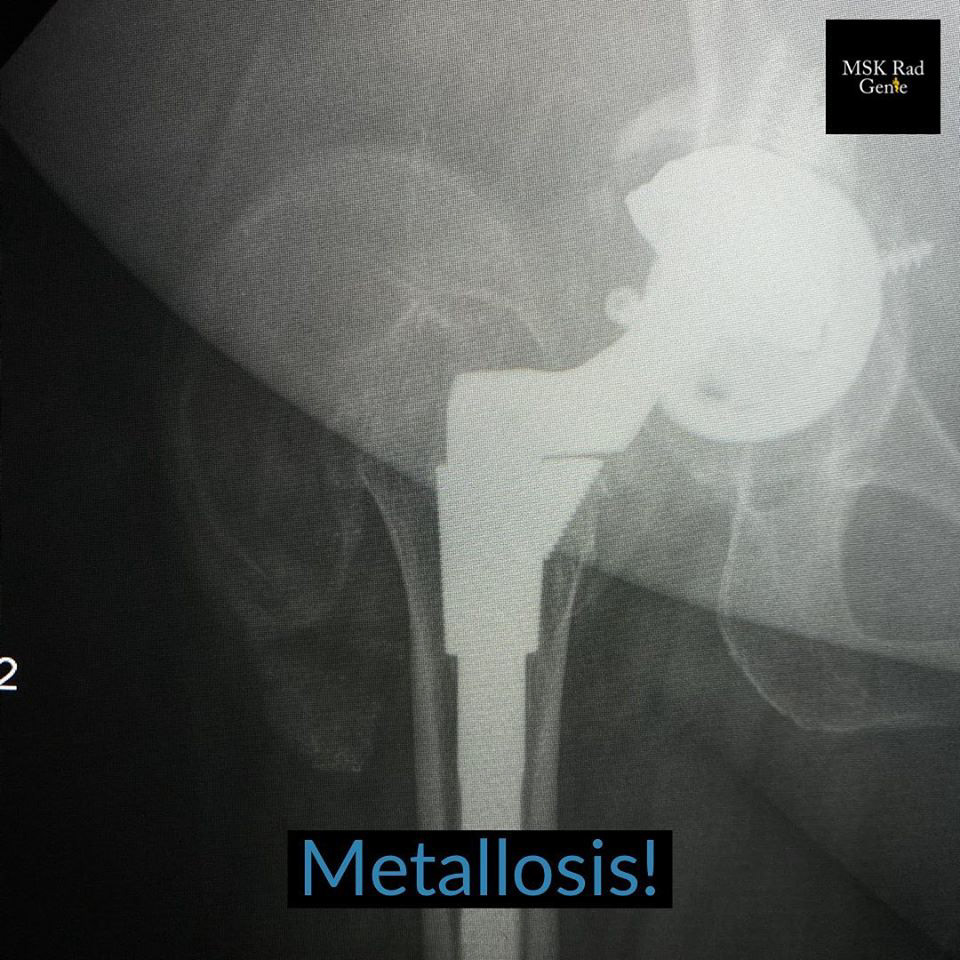

Metallosis! Hardware failure, especially in hip arthroplasties, can be a result of the following pathologies: 1. Simple aseptic loosening – diagnosed with progressive more than 2mm peri-hardware or peri-cement lucency and not associated to infection. Lucency about hardware is usually symmetric. 2. Infection – peri-hardware lucency greater than 2mm, but unlike loosening, usually asymmetric, focal and destructive. 3. Particle disease – previously discussed and related to debris released by hardware which in turn incites osteolysis of the surrounding bone. 4. Metallosis – also known as hardware pseudotumor and usually co-existing with particle disease and osteolysis. In imaging, metallosis is seen as a soft tissue pseudo mass created by metal debris. This mass usually is dense on radiographs and CT, due to the presence of metal. This case shows both particle disease with osteolysis at the greater trochanter and metallosis at the soft tissue adjacent to the greater trochanter. #mskrad #mskradiology #radiology #radiologia #radres #radtech #radiologyeducation #hipprosthesis #radiologyresident #msk🧞♂️